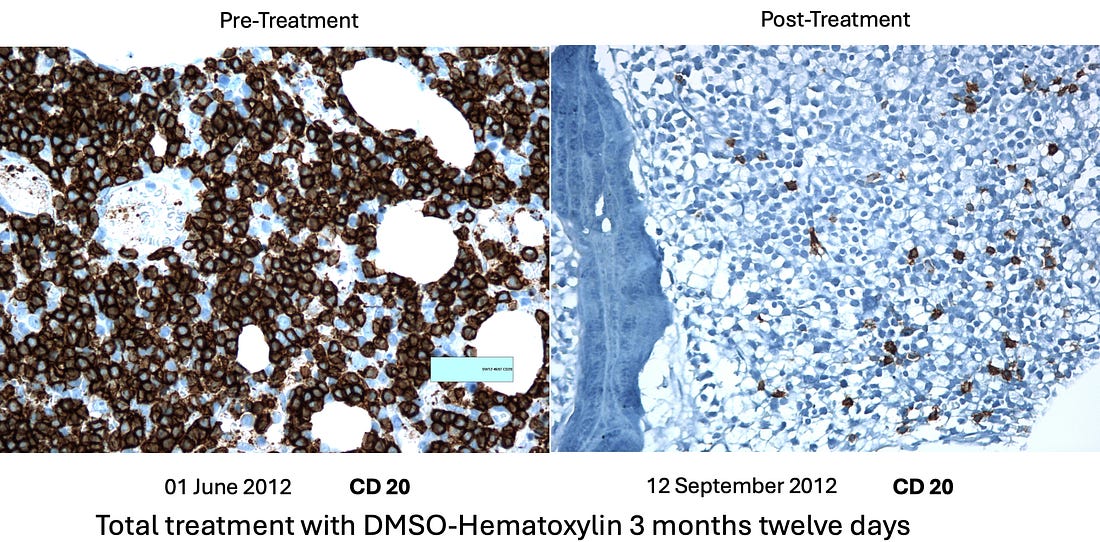

project involved treating approximately 85 patients, with the cure rate

but it is not perfect and will not work for everyone. •Leukemias (particularly acute leukemia) Note: myeloproliferative neoplasms (e.g., polycythemia vera, essential thrombocythemia and primary myelofibrosis) depend upon a mutant protein for survival which was shown to be susceptible to disruption by a few small compounds including hematoxylin. While D-hematoxylin has not been tested on these disorders, this study (along with the other known effects of DMSO and D-hematoxylin) suggest it could be an effective treatment for them. The cancers with a poorer response included: •“Solid” tumors Additionally, if there is a cancer marker associated with the tumor (e.g., CEA or PSA), it will often rapidly drop, making it very easy to track the progress of D-hematoxylin. As the following cases show, many of the improvements were quite profound: •A 54-year-old female patient with Classic Hodgkin Lymphoma which had invaded 72% of her bone marrow, with CD20-positive expression. She had a variety of symptoms (e.g., recurrent pleural effusions and anemia), but since her religion did not permit blood transfusions, she received only D-hematoxylin and EDTA and then had a full recovery (with no recurrence in twelve years of follow up). The most striking aspect of this case was the change in her bone marrow biopsy, after three months of treatment with D-hematoxylin (unlike chemotherapy) it selectively destroyed the cancerous cells, allowing normal ones to regrow and rapidly addressed her anemia. •A 72 year old patient with leukemia who was anemic and had her anemia rapidly improve following D-hematoxylin: Likewise, similar bone marrow changes were seen in her. Note: another similar leukemic patient on D-hematoxylin with anemia had no improvement. After investigating, it was determined this was due to her regularly using WD40 on a daily basis (without respiratory protection) and hence having a bone marrow intoxication which was directly damaging the bone marrow (and in turn the leukemia diagnosis may have been incorrect). •A 16 year old male with a mediastinal seminoma that received 16 D-hematoxylin infusions, 5 IV vitamin C infusions and then one chemotherapy session (on July 7) where cisplatin and bleomycin were combined with DMSO (after which he continued chemotherapy and has recovered from the cancer). •A 63-year-old male with cholangiocarcinoma (a rare, aggressive and notoriously difficult to treat cancer of the bile duct) who received D-hematoxylin plus chelation and vitamin C (but no chemotherapy). During his successful treatment, a drain from his bile duct was also monitored for tumor markers. Additionally, the cancer debris could be seen in the drainage tube (an internal-external percutaneous transhepatic biliary drainage catheter)—something which the Ecuador doctors now view as essential to have if D-hematoxylin will be used in this cancer: Note: another bile duct cancer patient (a 68 year old female) received palliative D-hematoxylin while waiting for surgery and chemotherapy (which ultimately could not be done because of how advanced the cancer was). Her cancer markers levels significantly improved following D-hematoxylin (and continued to reduce during gaps in treatment), but she eventually lost the will to live and passed after 16 months. •A 63-year-old man with B-cell lymphoproliferative disorder who received D-hematoxylin for 10 days (with no other treatment), experienced a significant drop (normalization) of his white blood cell count during that time then stopped at the advice of his hematologists, and two years later died from COVID. •A man who had a stable bladder polyp which became cancerous following a covid vaccination (with the initial sign being a large blood clot in the urine) which when examined had spread in a large portion of the urinary tract’s endothelium. It was surgically removed, but due to how far it had spread, the urologist told the patient he would only survive for two months. They then began five weeks of intravesical and IV D-hematoxylin, and in four years, the cancer never returned (which led to the urologist telling everyone about the “amazing” surgical procedure they had performed). •A 55-year-old female who had a mediastinal tumor (type unknown as it was wrapped 560° around the aorta and hence could not be biopsied) which fully resolved after 33 daily D-hematoxylin treatments. Additionally, this was the CT prior to treatment where the tumor can be seen around the aorta: While this was the CT two weeks following the D-hematoxylin treatment: Lastly, at five years follow up, there was no recurrence. •A 27-year-old female with acute lymphoblastic leukemia reacted poorly to two sessions of chemo, was classified as terminal, and then was started on D-hematoxylin. She had a significant improvement in her cancer and simultaneous improvement in her anemia which continued long after conventional treatments for anemia were halted (which did not include blood transfusions as she was a Jehovah’s Witness). In a before (1-2-2020) and after (2-1-2020) video I saw of this patient, she initially looked very frail and had difficulty walking, while just a month later (after 31 days of treatment), she had no difficulty walking and looked vibrant and robust. Additionally, they continued to monitor her on a monthly basis, and four years later, she’d had a healthy baby, and had her hematocrit range from 42 to 48 (which is slightly above average) indicating she had no further risk of anemia (even though hematologists in the hospital had predicted her reckless pregnancy would cause severe anemia). Additionally, her ESR (which had been significantly elevated prior to treatment) normalized (and remains normal 5 years later). Lessons from EcuadorIn addition to observing a remarkable degree of success from D-hematoxylin, the Ecuadorian team was able to discern a variety of patterns (many of which mirrored Tucker’s previous observations) that helped craft their treatment protocols. For example: •While DMSO alone can somewhat help with cancer, the effects of DMSO combined with hematoxylin are completely different from what would be observed with DMSO alone. •They saw many signs during their treatment protocols that D-hematoxylin selectively targeted cancer cells. •Cancers did not develop resistance to D-hematoxylin (which is a common challenge with many chemotherapies). •While some tumors rapidly disappear, other types frequently become avascular (which stops their growth) and dried-out, blanched, or fibrous rather than being directly shrunk (e.g., I reviewed cases where a brain cancer simply stopped growing). In many cases, those tumors are then very easy to extract surgically. Note: to my knowledge, everyone besides that Ecuadorian team who treats with D-hematoxylin still uses Tucker’s protocol and has not tried to improve upon it. Variations in D-Hematoxylin EfficacyOn